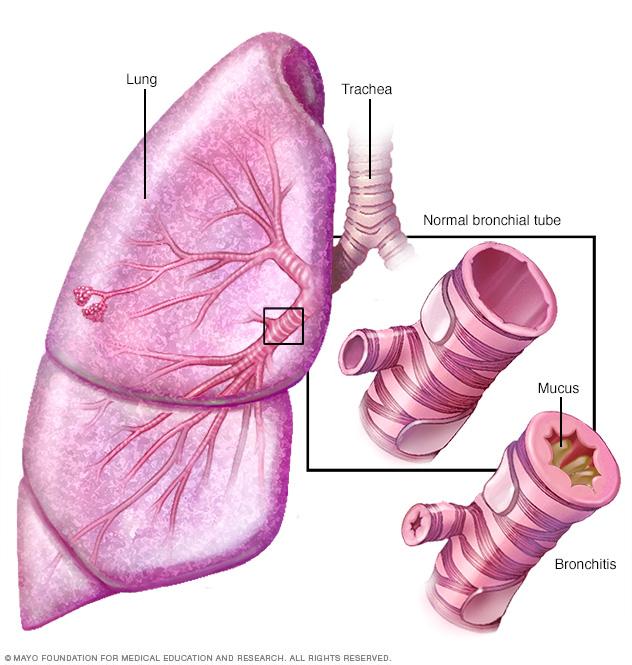

Bronchitis

Bronchitis is an inflammation of the lining of the bronchial tubes, which carry air to and from the lungs. People who have bronchitis often cough up thickened mucus, which can be discolored.

- Chronic bronchitis. In this condition, the bronchial tubes become inflamed and narrowed. As a result, the tubes thicken, making less room for air to pass through. Extra mucus caused by the irritation blocks the narrowed tubes even more. An ongoing cough results from trying to clear mucus from the airways.